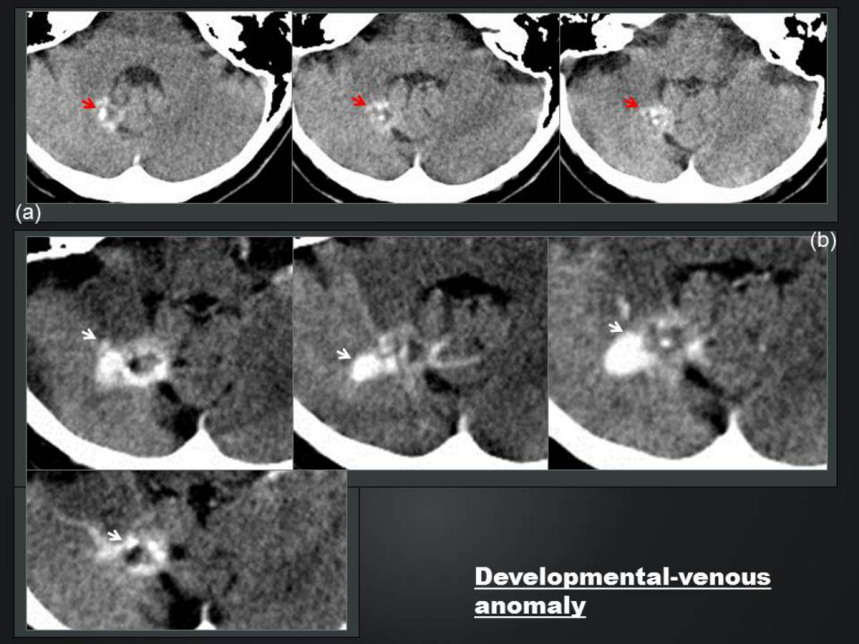

cf4dfc78387e68fa8b866fdb2fa26070.png

静脉发育不良,多发细小结节钙化聚集(白箭头);增强之后周围「水母头」样